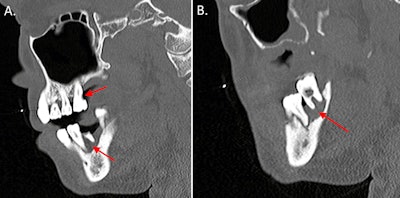

A CT scan of the maxillofacial area with contrast revealed endodontic and periodontal disease involving the molars, and magnetic resonance imaging (MRI) of the lumbar spine with and without contrast showed discitis at L4-L5, with abnormal enhancement of anterior paraspinal soft tissues from L4-S2. The MRI of the cervical spine showed a soft-tissue lesion, likely an abscess, with surrounding edema and enhancement. There was no evidence of osteomyelitis, discitis, or epidural abscess in the cervical spine, they wrote.

(A) A CT scan with contrast shows the sagittal view of the man's endodontic and periodontal disease of the right teeth (red arrows). (B) A CT scan with contrast shows the sagittal view of the patient's periodontal disease of the left teeth (arrow). Images courtesy of Munoz et al. Licensed by CC BY 4.0.